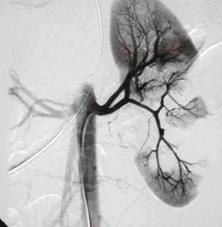

Rinichiul stang

Sistem

caliceal, ureter, vezica urinara ocupate de un cheag de sange

Lipsa vascularizatiei rinichiului stang Angiograma

Lipsa vascularizatiei rinichiului stang